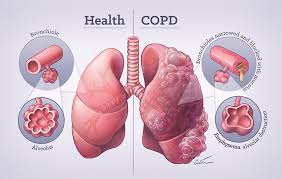

सीओपीडी एक दीर्घकालिक फेफड़ों की बीमारी है, जिसमें सांस की नलियाँ संकरी हो जाती हैं और फेफड़ों में सूजन आ जाती है। इसके कारण सांस लेने में कठिनाई, लगातार खांसी और बलगम बनता है। यह बीमारी समय के साथ धीरे-धीरे बढ़ती है।